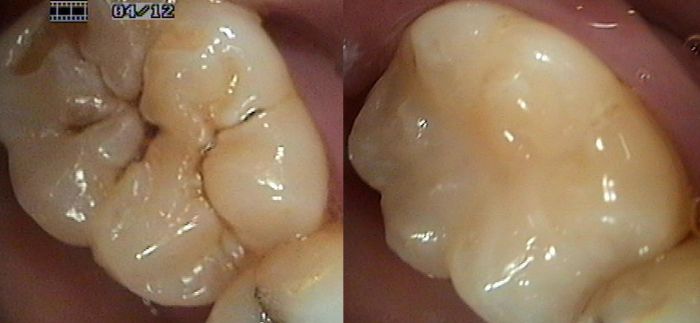

What is a sealant restoration?

To answer this you need to know what a tooth fissure is. Fissures are the nooks & crannies on the biting surfaces of the permanent “chewing” teeth (molars & premolars). These areas help the chewing process to mash up your food. These areas commonly decay as food gets trapped in them. Tooth brush bristles aren’t long enough or thin enough to remove this food.The food stagnates & the decay process begins. Using air abrasion technology & plaque & decay detecting dye, it is now possible to thoroughly clean these pits & fissures ensuring there is no decay ors food debris present. The fissure is then sealed with a long lasting, flowable, light cured white filling material.